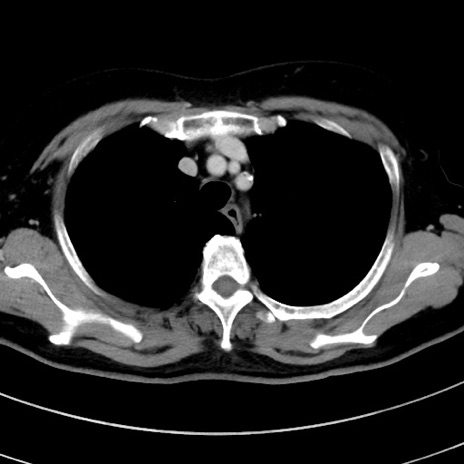

症例9(横断像)

【症例】 60歳代女性

【主訴】むかつき、みぞおちの痛み

【現病歴】3日前よりむかつきがあり、食事がとれない。

【既往歴】糖尿病

【身体所見】発熱なし、心窩部圧痛軽度あるも、腹膜刺激症状なし。

【データ】WBC 7400、CRP 1.92